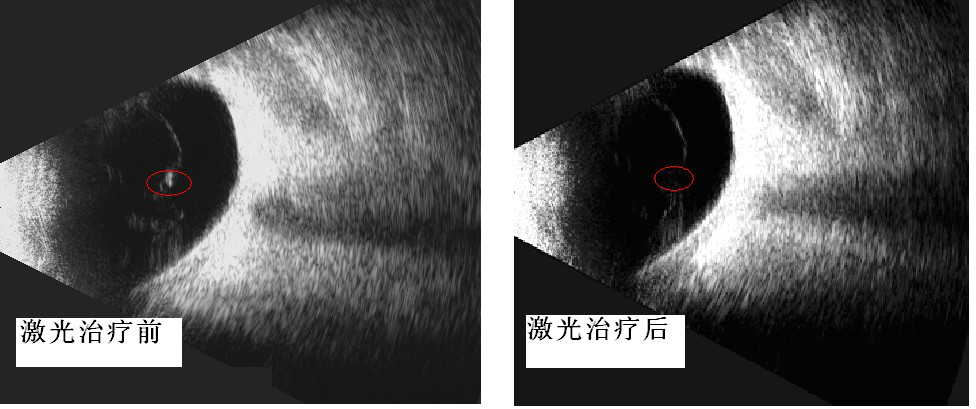

已为首批飞蚊症患者进行治疗,这些患者倍受飞蚊症折磨,通过2-3次玻璃体激光消融治疗,取得了满意的疗效。从眼部B超检查也显示激光治疗前后玻璃体混浊也有了明显的改善。